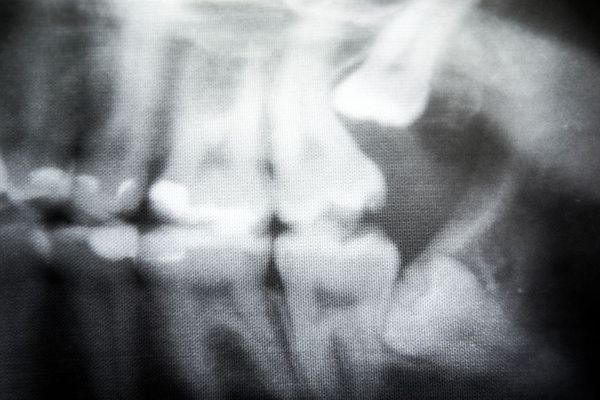

Impacted Wisdom Teeth

Most of the time, an impacted wisdom tooth is easy to diagnose during a routine dental exam . During the exam, your doctor can perform a visual evaluation of your bite and review digital x-rays to determine where and how the tooth has become impacted. For more complex impaction, the doctor can also use 3-D imaging technology for a clear view of all the tissues involved.